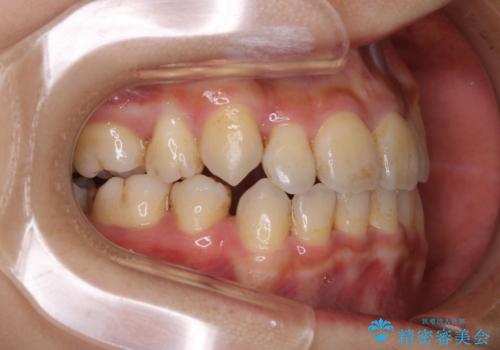

PMTC60分コースを行いました。紅茶による着色が全体的に付着していました。

インビザライン中の患者様で、紅茶を飲んだ後にそのままマウスピースをはめていたそうです。着色が、かなり目立っていた為、追加アライナーのタイミングで全体の着色を除去し、とても綺麗になりました。